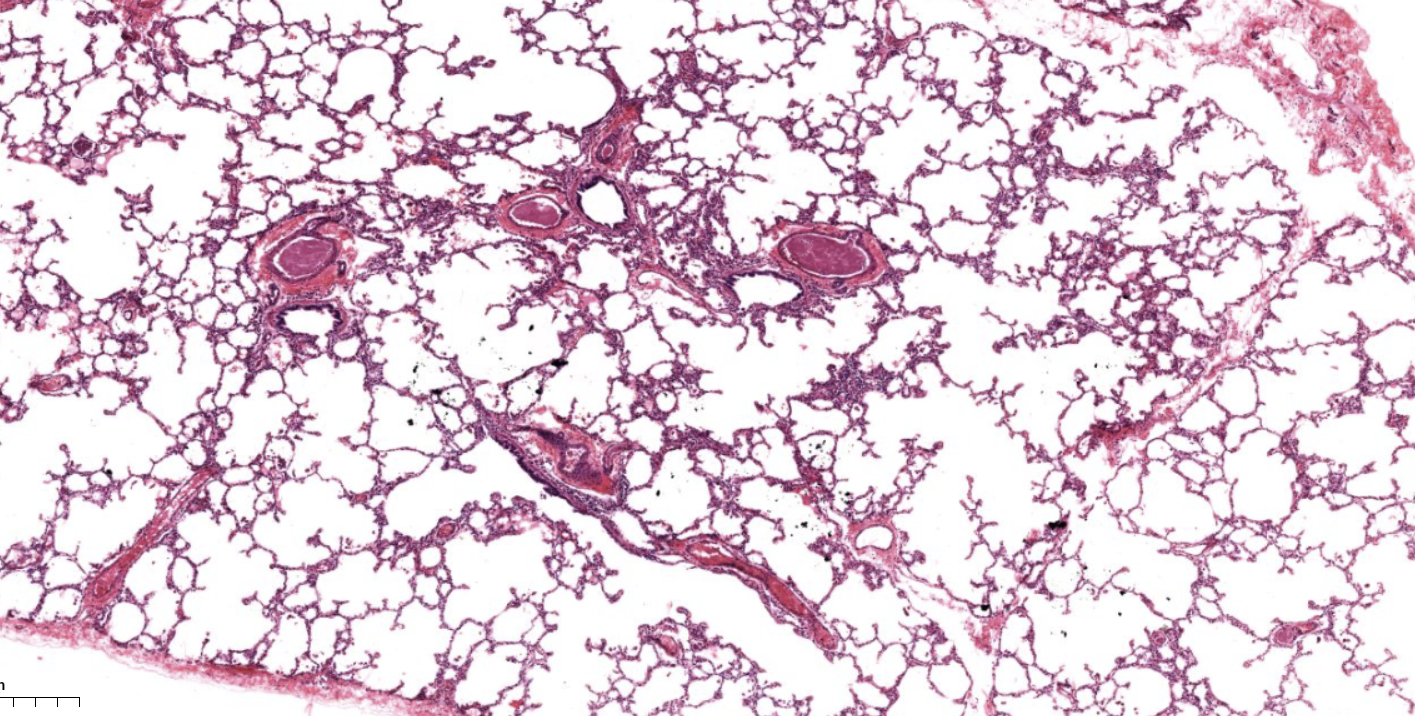

Lung tissue

NOTICE: THE OPEN SPACE OF THE ALVEOLI